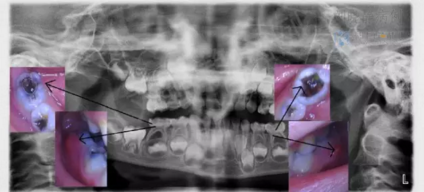

真相解密:寶寶乳牙要?dú)⑸窠?jīng)?關(guān)于乳牙根管治療史上最強(qiáng)圖解

寶寶牙齒疼得不行,去醫(yī)院找牙醫(yī)就診,經(jīng)??梢月牭竭@樣的兩種回答:“孩子的這顆牙齒需要?dú)⑸窠?jīng)了”“孩子的這顆牙齒需要做根管治療了”...

粑粑麻麻擔(dān)心了,牙神經(jīng)都去除了,對寶寶今后換牙會(huì)不會(huì)有影響?

為了能夠幫助粑粑麻麻更好的解除疑惑,小科以一則漫畫形式給家長科普一下乳牙根管治療的相關(guān)知識(shí)。

關(guān)于根管治療,你是否還有以下疑問?

牙疼就要做根管治療嗎?

小科:不一定,但大部分情況都是。因?yàn)檠捞鄞蟛糠质驱x壞深入到牙本質(zhì)引發(fā)的。也要看牙齒具體情況,如果拍片子檢查后,齲壞已經(jīng)滲入牙本質(zhì)深層,引發(fā)了牙髓或根尖炎癥,就是牙齒內(nèi)部出現(xiàn)了炎癥,那就需要做根管治療了。

根管治療是如何給牙齒消炎止疼的?

小科:根管治療是通過開髓后,將牙齒打開,對牙齒內(nèi)部,有炎癥病變的地方進(jìn)行清潔,清除腐壞物質(zhì),不斷沖洗后,再放置消炎藥物,最后將牙齒封好,牙齒內(nèi)部問題逐漸就能消失了。

根管治療為啥需要多次就診?還要反復(fù)拍牙片?

小科:根管治療術(shù)并非一次完成治療,醫(yī)生需根據(jù)患者臨床檢查情況,分步分次進(jìn)行治療。全部療程患者需到就診2—3次,甚至4—5次,每次間隔1周左右。

醫(yī)生不是掃描儀,也沒有透視眼,為了解患牙的牙根形態(tài)、走向、長度及根尖周有無病變及病變大小,醫(yī)生常常要求患牙在根管治療術(shù)前,術(shù)中和術(shù)后分別拍X線片,以幫助診療。

根管治療后牙齒使用壽命有多長

小科:根管治療是幫您拯救了一顆牙齒,恢復(fù)牙齒的原有功能,壽命也很長;再者,治療后的患牙會(huì)使用一些修復(fù)方式保護(hù)起來,比如做牙冠,以延長患牙壽命。而修復(fù)后的患牙因?yàn)闆]有牙神經(jīng),失去了對外界刺激的感知。所以,要比普通牙齒多一些關(guān)注,聽從醫(yī)囑,正確維護(hù)使用。